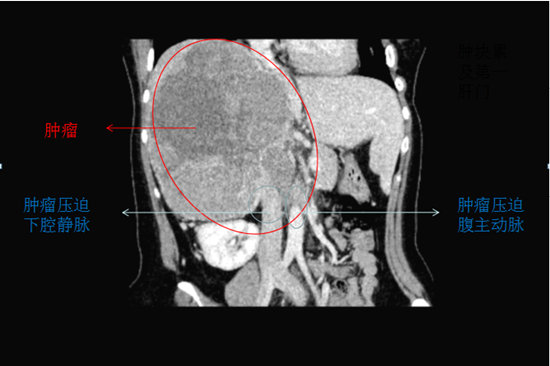

患者一個(gè)月前感覺右腰部脹痛,隨后出現(xiàn)雙下肢水腫,遂至當(dāng)?shù)蒯t(yī)院就診,檢查結(jié)果提示:右腎腫瘤并侵犯下腔靜脈,無(wú)法完成超高難度手術(shù),建議轉(zhuǎn)上級(jí)醫(yī)院治療。

轉(zhuǎn)至中南大學(xué)湘雅二醫(yī)院就診,急診科張東山教授聯(lián)合泌尿外科張磊副教授會(huì)診并為患者進(jìn)一步檢查,發(fā)現(xiàn)患者肝臟、腹膜后淋巴結(jié)、肝右靜脈及下腔靜脈都被侵犯并轉(zhuǎn)移。

患者右側(cè)肝腎間隙巨大腫塊及肝臟轉(zhuǎn)移灶緊臨右肝靜脈、壓迫下腔兩大主要靜脈及膽管,且兩大靜脈已被腫瘤侵犯,術(shù)中稍加不小心,隨時(shí)會(huì)造成大出血。右腎、右輸尿管受壓、積水,腹腔內(nèi)失去正常的解剖結(jié)構(gòu),加上患者既往有甲亢病史及高泌乳素血癥,對(duì)手術(shù)操作、麻醉及術(shù)后管理均提出了極大的挑戰(zhàn)。